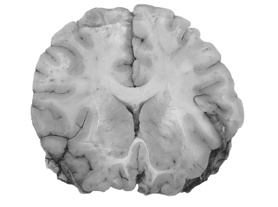

д) Несложно увидеть, что белое вещество и нервные волокна занимают значительную часть мозга: все его отделы посылают информацию в другие участки, зачастую весьма удаленные [544].